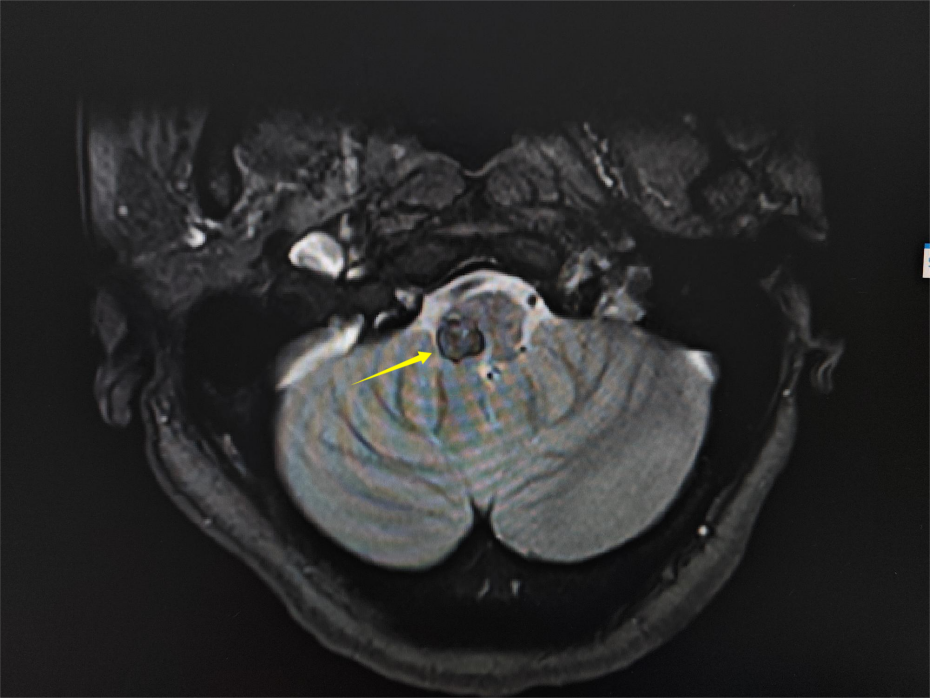

術(shù)前影像

患者李阿姨,54歲,因“右側(cè)肢體無力”入院。她在當(dāng)?shù)蒯t(yī)院做了顱腦CT,提示腦干出血,經(jīng)相關(guān)藥物治療,未見明顯效果。在朋友介紹下,李阿姨找到了惠州三院神經(jīng)外科負責(zé)人景英朝主任醫(yī)師。結(jié)合病史和查體,進一步完善顱腦磁共振等檢查,醫(yī)生發(fā)現(xiàn)腦橋左側(cè)有一類圓形占位,信號不均勻,考慮腦干海綿狀血管瘤可能性大,需要住院治療并完善檢查!

景英朝主任醫(yī)師介紹,海綿狀血管瘤是由眾多薄壁血管組成的海綿狀異常血管團,并非真性腫瘤。海綿狀血管瘤有反復(fù)多次出血的特點。由于腦干內(nèi)存在重要的神經(jīng)傳導(dǎo)束和眾多神經(jīng)核團,腦干海綿狀血管瘤出血可引起嚴(yán)重的神經(jīng)功能障礙,給患者帶來災(zāi)難性后果。經(jīng)學(xué)科討論,患者手術(shù)指征明確,需手術(shù)切除海綿狀血管瘤,以減少出血導(dǎo)致嚴(yán)重神經(jīng)功能障礙的風(fēng)險。